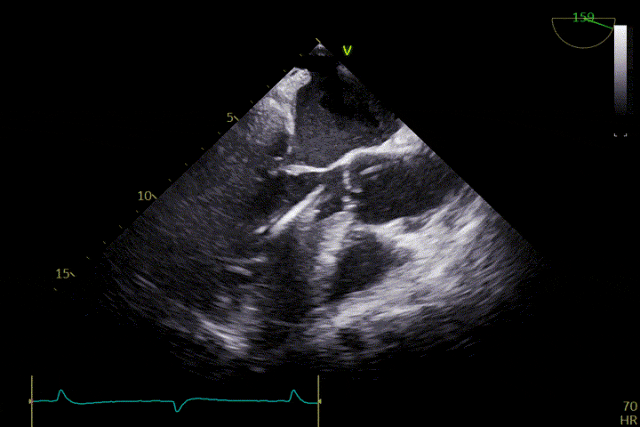

術前超聲